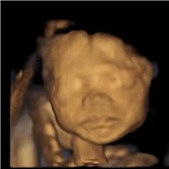

三维看到娃好激动

1个月前 收录

阅读:5.8万回复:59